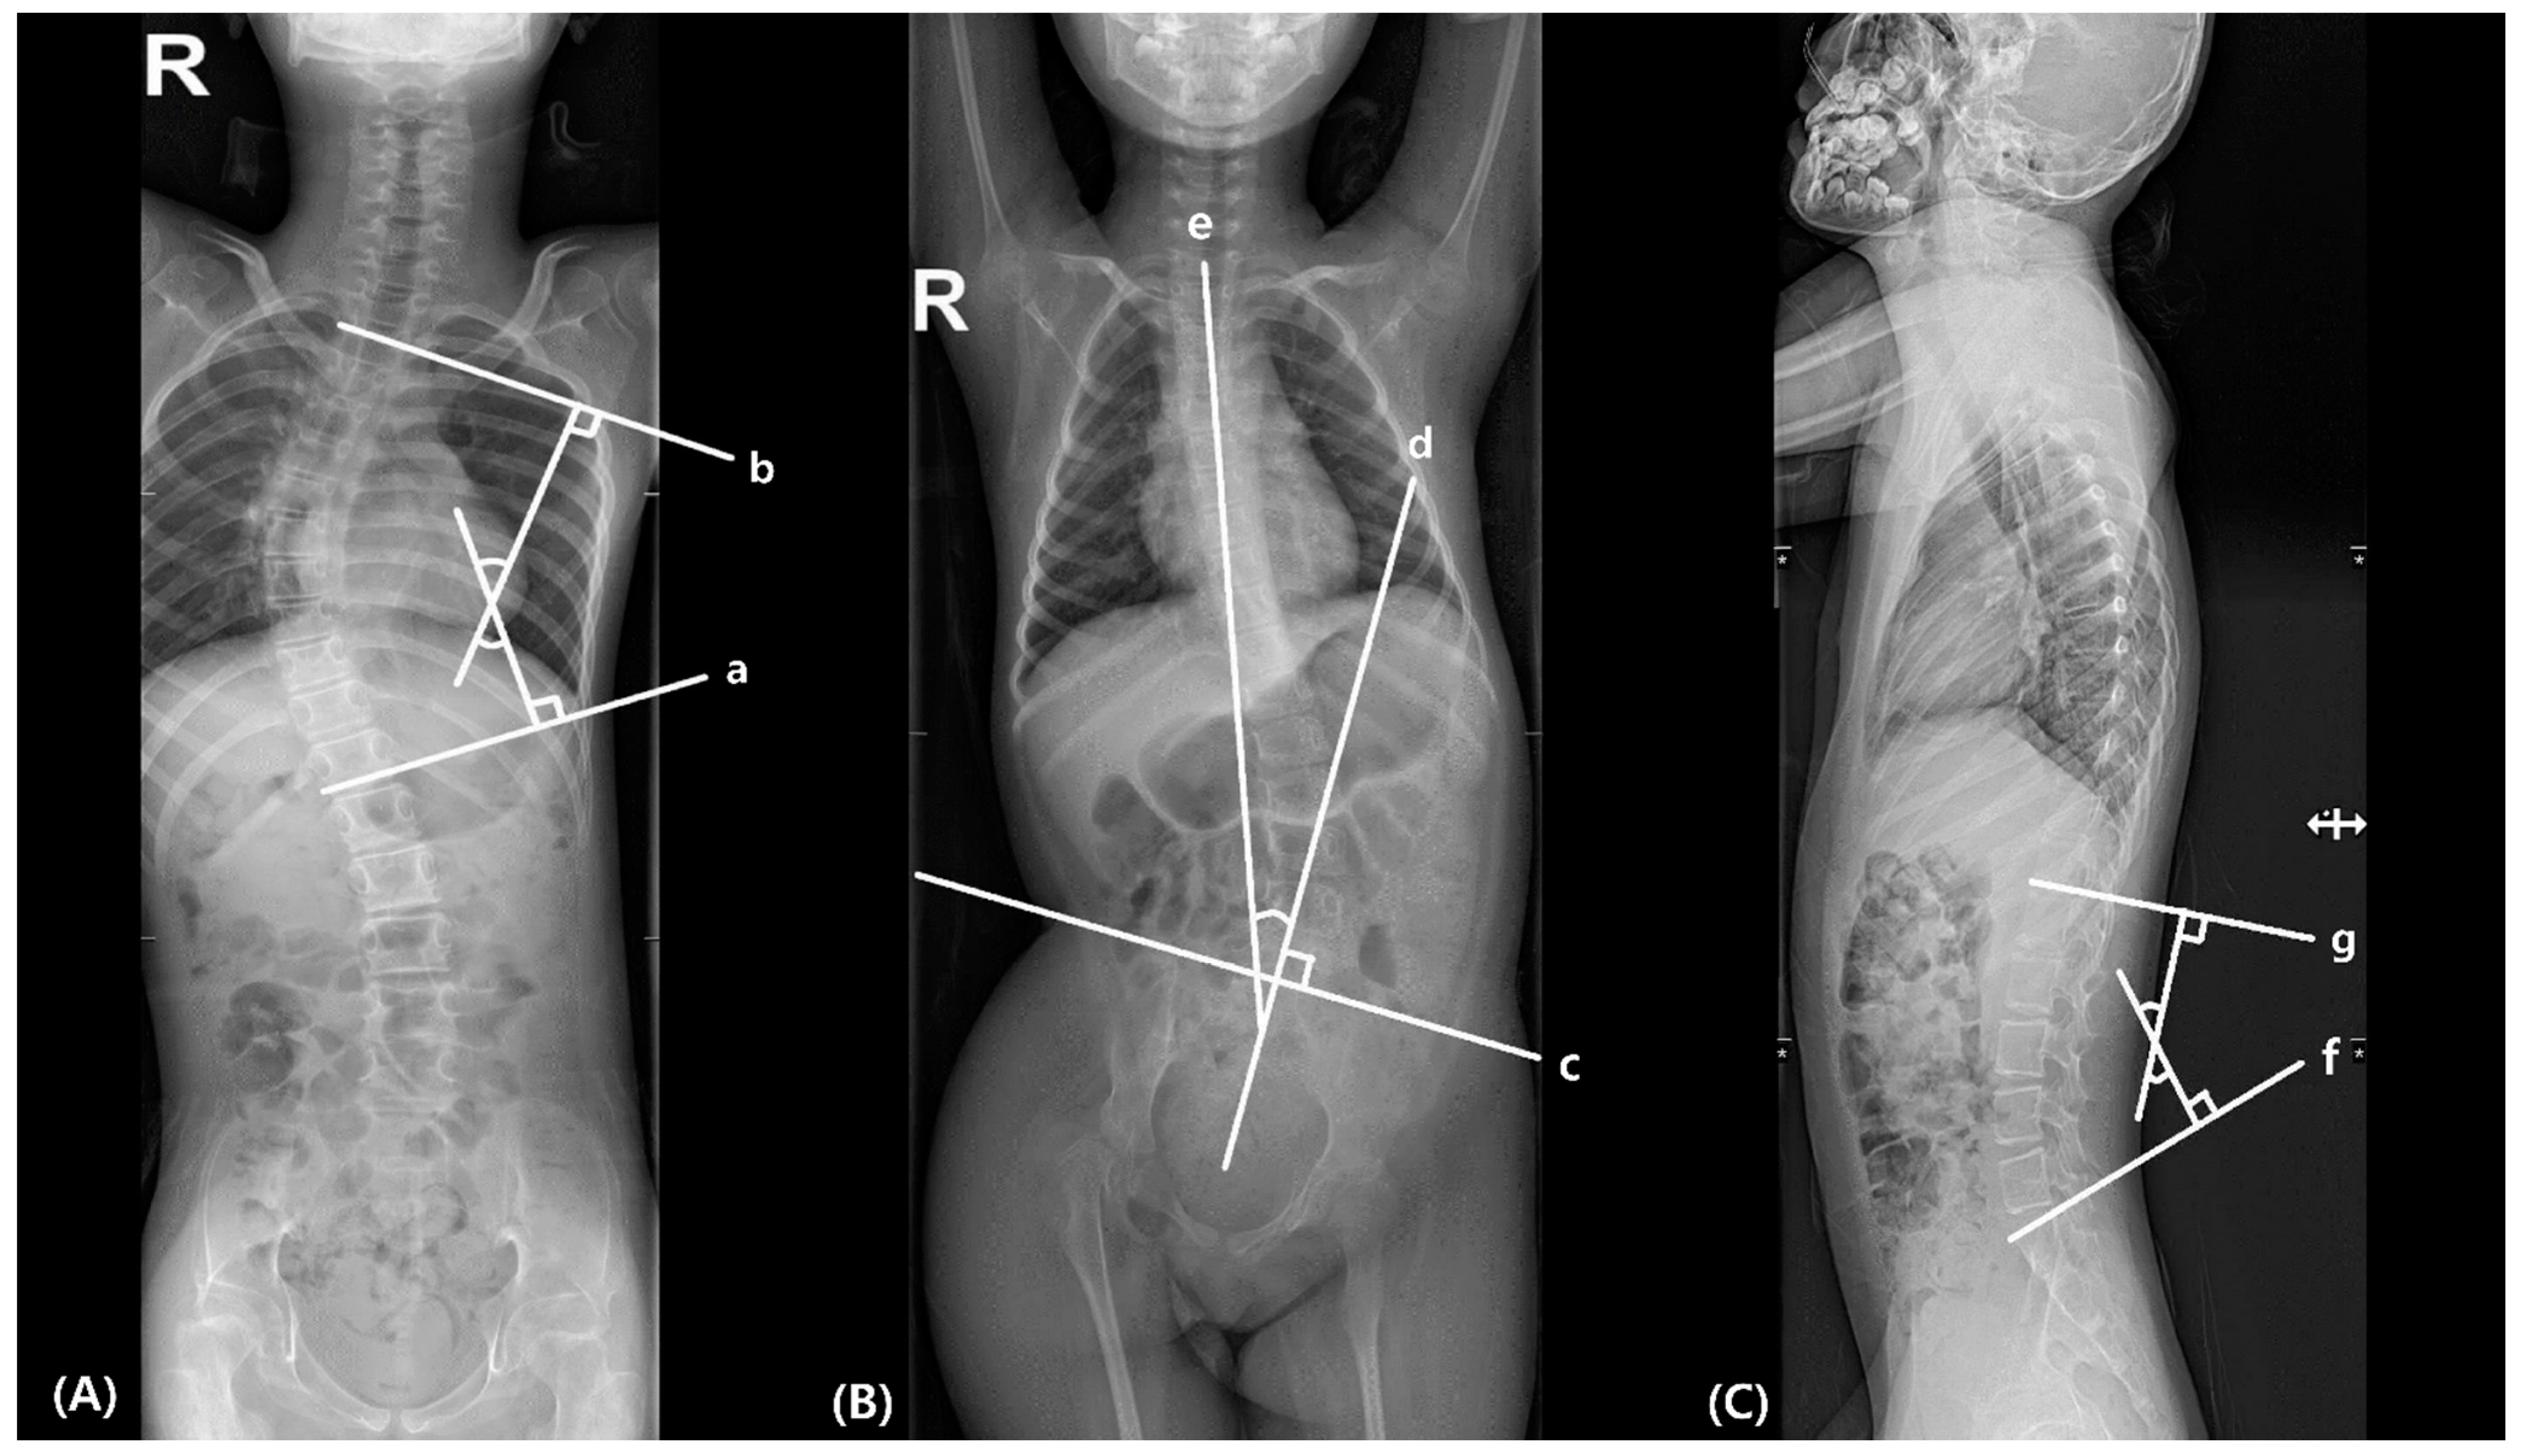

2.2.1. Scoliosis

2.2.2. Pelvic Obliquity (PO)

2.2.3. Lumbar Lordosis

2.2.4. Vertebral Rotation